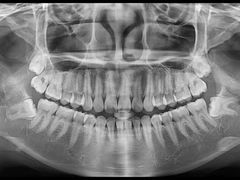

• 南方医科大学口腔医院(番禺院区)

• -南方医科大学口腔医院(番禺院区)